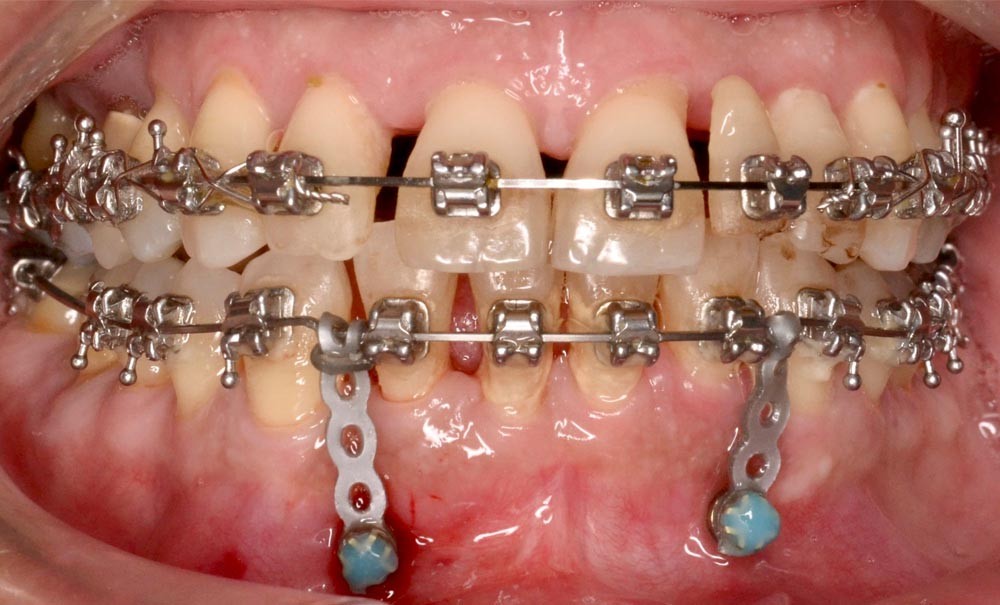

Le traitement d’orthodontie est réalisé en technique multi-attache vestibulaire (TGO, GC Corporation, Tokyo, Japon). La dent 46 n’est pas prise en charge dans l’appareillage, étant donné son faible ancrage et son pronostic réservé. L’alignement initial est effectué sur un arc Niti .016 au maxillaire et en trois segments à la mandibule (Niti .018x.025 en postérieur et Niti .016 de 33 à 43) (fig. 6).

En raison de l’ancrage dentaire postérieur mandibulaire très limité, il est décidé d’utiliser des ancrages osseux pour l’ingression du bloc incisivo-canin mandibulaire, afin de niveler l’arcade et de recréer le surplomb nécessaire à la fermeture des diastèmes maxillaires. Deux minivis d’ancrage sont positionnées entre les dents 32/33 et 42/43, après réalisation d’un examen CBCT localisé sur l’arcade mandibulaire (fig. 7 et 8). Ces minivis antérieures ont été rapidement déposées, en raison de leur mobilité et de la gêne importante de la patiente liée au positionnement très apical du fait de l’alvéolyse.